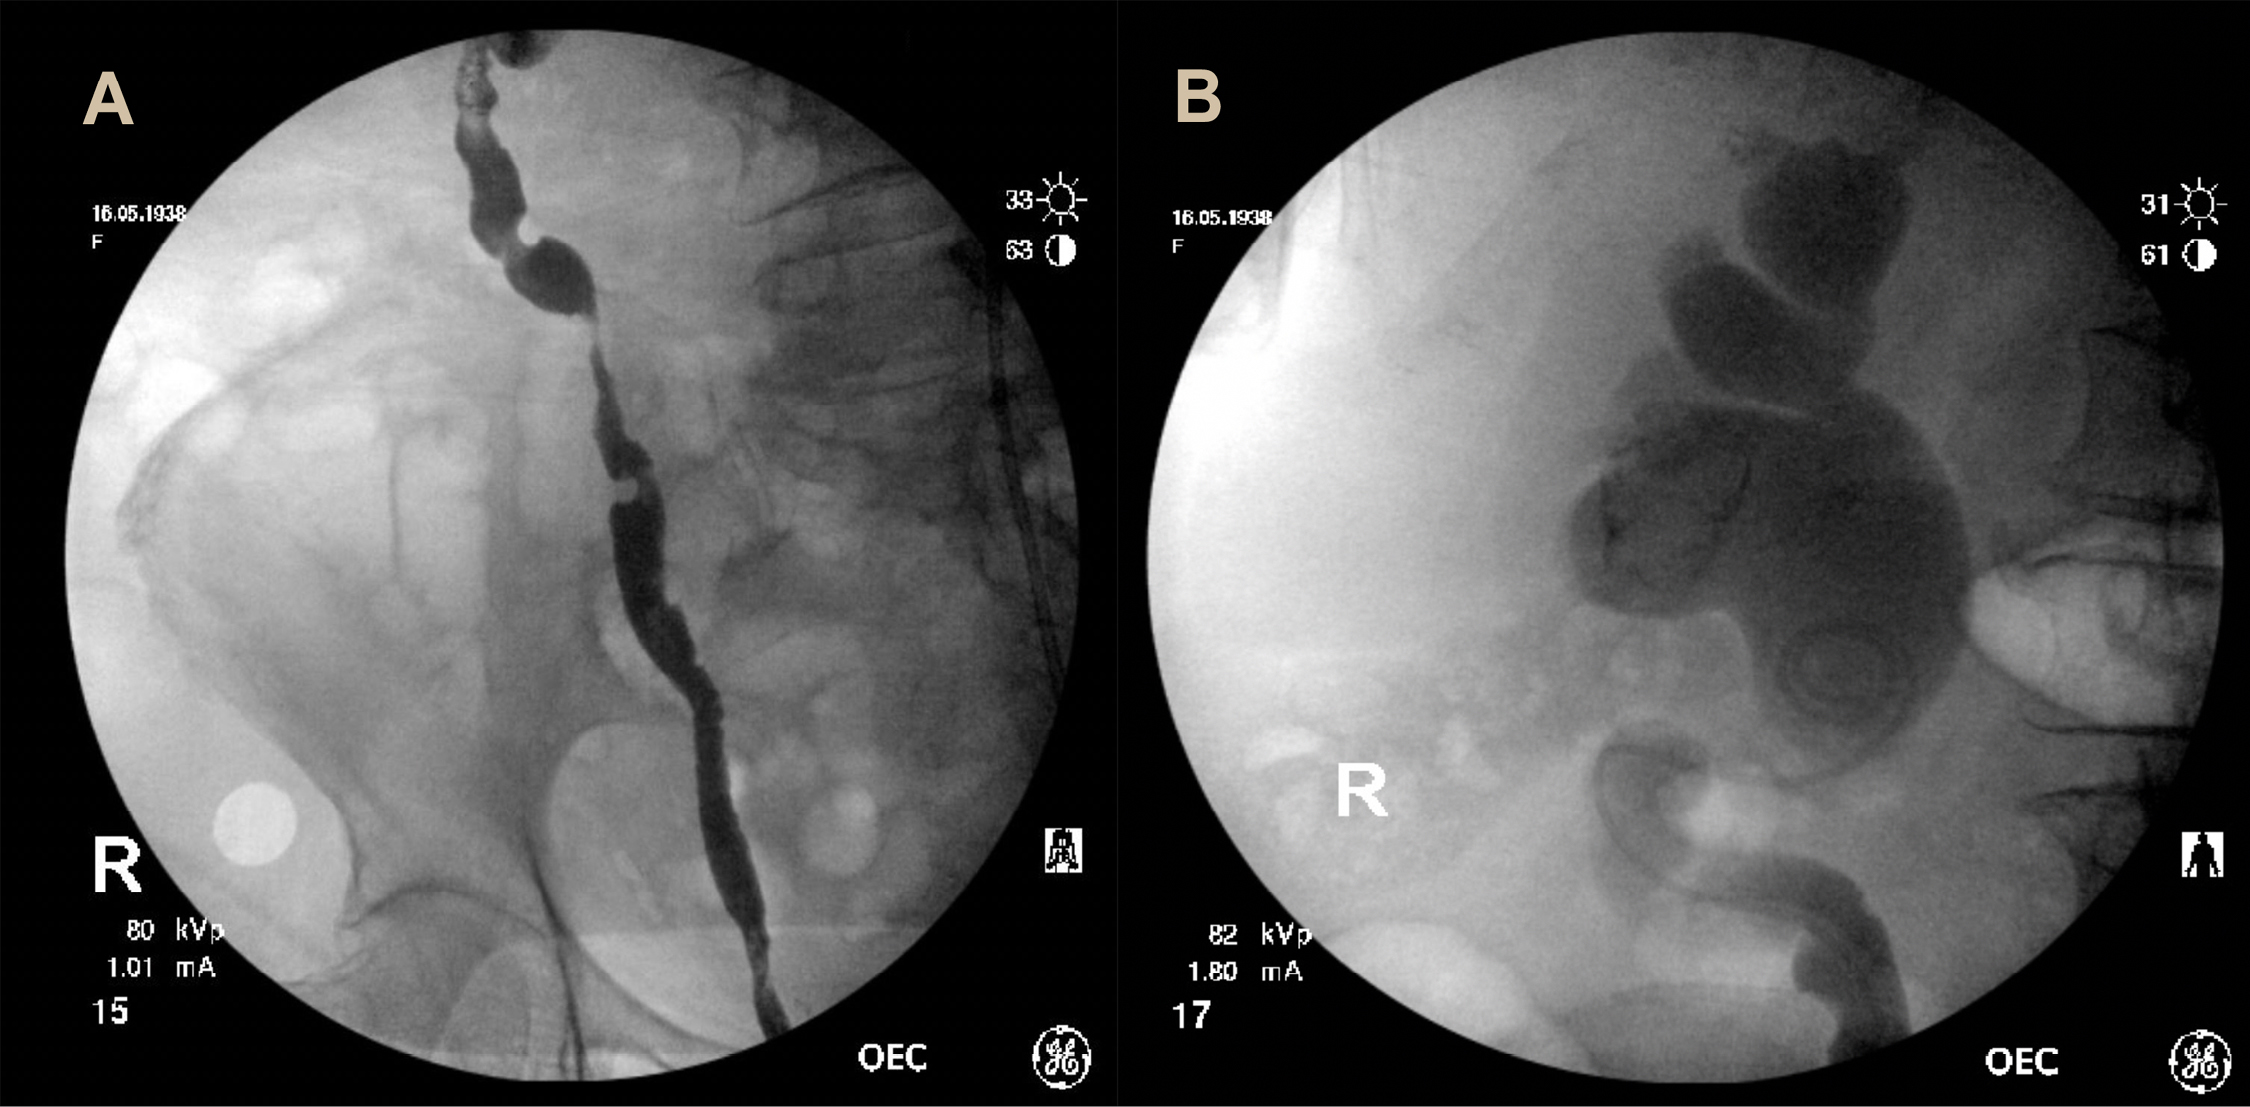

An 82-year-old female presented to the emergency department with rigors, lethargy and back-pain. She reported 12 months of worsening lower urinary tract symptoms with irritative voiding, urgency and recurrent pan sensitive Escherichia coli (E. coli) urine infections. Background history included insulin-dependent diabetes mellitus and non-Hodgkin’s lymphoma, though a she was a non-smoker, and had no occupational exposure to carcinogens. On presentation she was septic. Her abdominal examination was unremarkable. Blood tests revealed a white cell count of 5.4 × 109/L, a haemoglobin of 96 g/L and a serum creatinine of 234 µmol/L. Urine dipstick revealed leukocytes without nitrites or red cells. A non-contrast computed tomography (CT) abdomen showed severe bilateral hydroureteronephrosis and marked thickening of the bladder base involving both vesico-ureteric junctions, suggestive of transitional cell carcinoma (Fig. 1). Antibiotics and resuscitation were commenced, a catheter placed and a cystoscopy arranged.

Figure 1. Computed tomography—coronal (A) and axial (B) planes demonstrating bilateral hydroureteronephrosis and a bladder mass at the base measuring 13 mm.